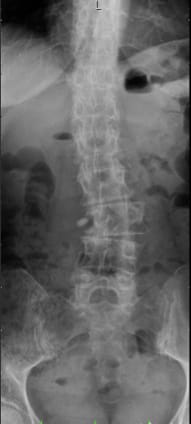

Torsional scoliosis of the lumbar spine measuring 40° (left image) Dynamic corrective spondylodesis with flexible carbon fixator (right image)